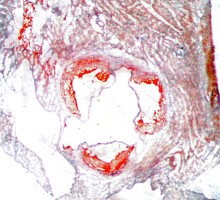

Atherosclerosis Aortic Root Histology Examples

Oil Red-O Staining (fat-soluble dye)